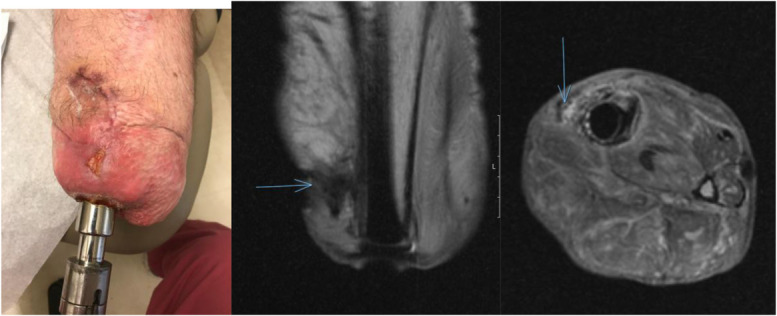

经皮骨锚定骨整合体中浅表和深层种植体相关感染的诊断、危险因素、治疗方法和长期后遗症尚不明确。与全关节置换术中诊断和处理假体周围关节感染的丰富经验相比,骨整合手术最近才在美国的少数骨整合中心被采用,导致缺乏长期结果。通过这些骨整合中心的经验,我们就经皮骨锚定骨整合术后感染并发症的围手术期管理、发生率、治疗和诊断提出了共识声明。

The diagnosis, risk factors, treatment algorithms, and long-term sequelae of superficial and deep, implant-related infections in transdermal, bone-anchored osseointegration are not well-defined. In contrast to the robust experience diagnosing and managing periprosthetic joint infections in total joint arthroplasty, osseointegration surgery has only recently been adopted at a small number of osseointegration centers in the United States, contributing to the lack of long-term outcomes. Through the pooled experience from these osseointegration centers, we present a consensus statement on the perioperative management, incidence, treatment, and diagnostic workup for infectious complications following transdermal, bone-anchored osseointegration.